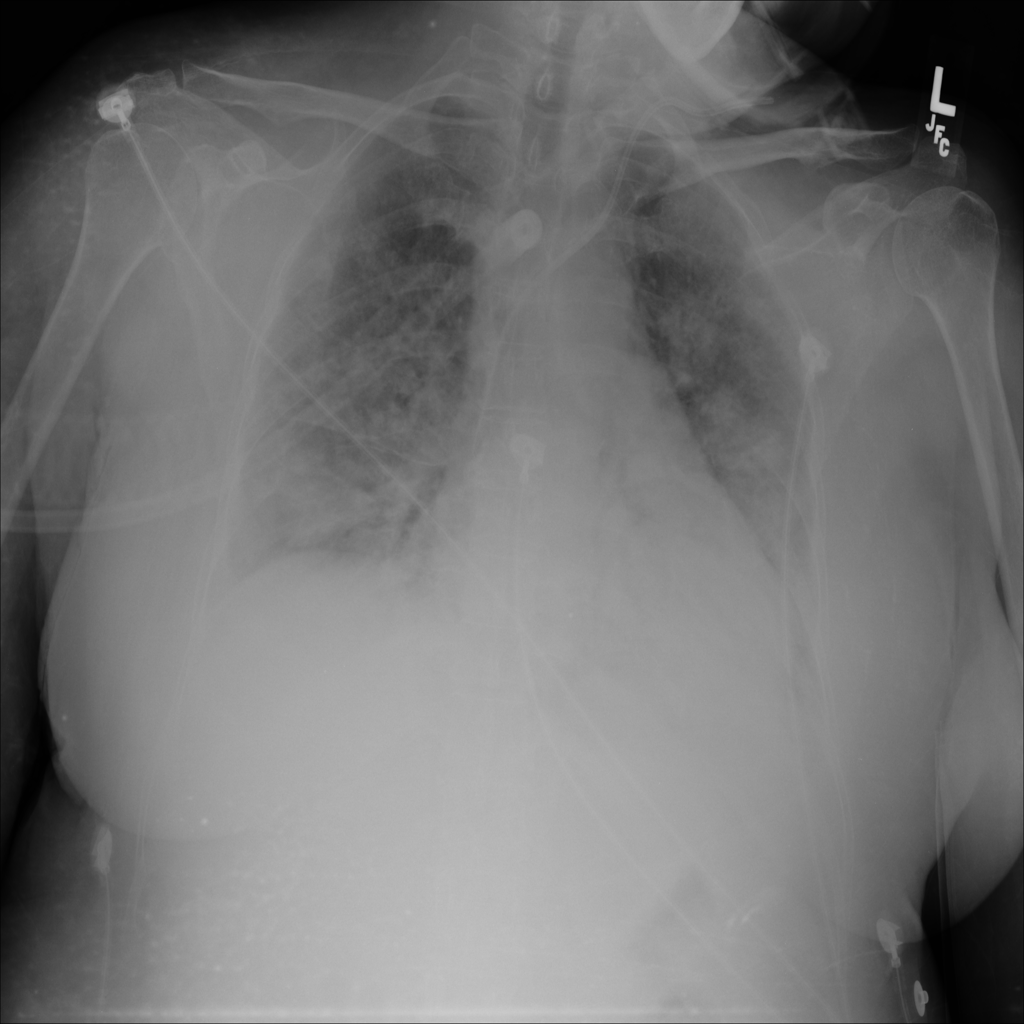

PAT-E828 · IMG-005Edema

PAT-E828 · IMG-005

AP